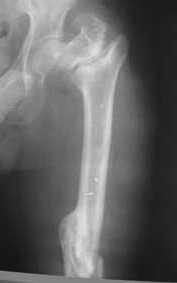

Возможно, пример (в приложении) поможет Вам определиться с выбором тактики лечения (у нашего пациента, кроме тугого ложного сустава вертельной области, сложная деформация н/3 бедренной кости; т.к. это не имеет значения к обсуждаемой теме - оставил "за кадром"). Как Вы видите, мы в данном случае не вводили чрескостные элементы в зону установки имплантата. При отказе от наложения опоры на таз (кстати, она не обязательно может быть громоздкая спицевая; арки со стержнями-шурупами, введенными в крыло подвздошной вполне достаточно) "не удивляйтесь", если опора со стержнями-шурупами, введенными в вертельной области в скором времени дестабилизируется, возникнет воспаление мягких тканей у чрескостных элементов. Такая опора "имеет на это право": нагрузка конечности от вершины дистального фрагмента до кончиков пальцев ляжет на нее. А двух-трех введенных рядом стержней-шурупов, как их не разноси от фронтальной плоскости, в данном

случае явно недостаточно для адекватной фиксации. + для того, чтобы выбрать оптимальные чрескостные элементы для промежуточной и дистальной опор, можете воспользоваться атласом